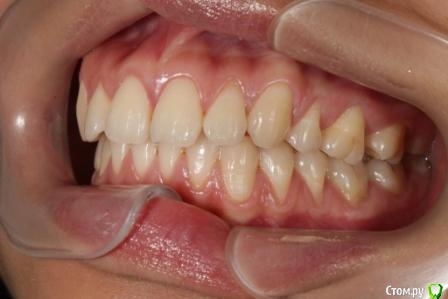

Головные боли, артроз ВНЧС, дистальный глубокий прикус, удалены 4ки на вч и 5 на нч

Сейчас мне 25 лет. С детства был дистальный глубокий прикус, зубы на верхней челюсти выпирали вперед, на нижней челюсти присутствовала скученность, из-за чего была удалена "мешающая" 5ка. Вероятно, этот зуб стоило сохранить.

В 2007-2008 гг. проходила ортодонтическое лечение с удалением 4ок на верхней челюсти. Резцовые зубы были перемещены назад, эстетически результат был удовлетворительным. Однако, проблема неправильного прикуса решена не была.

То, что эти боли могут быть следствием проблем с ВНЧС, узнала в последнюю очередь. МРТ показало, что у меня артроз суставов - 3 степени слева, полная вентрально-латерация дислокация суставного диска без репозиции; 1 степени справа, с репозицией, гипермобильность правого сустава. Асимметрии лица нет, однако рот открывается по S-образной траектории (почти не заметно), при широком открывании рта очень редко слышен щелчок, хрустов нет, слегка выпирает правый сустав. Заключение по МРТ с подробным описанием в приложении.

Была на консультации у ортопеда, который в качестве решения предложил выдвинуть нижнюю челюсть вперед с помощью ношения ортотика и брекет-системы. При этом перед началом и в ходе лечения указал на необходимость удаления 8ок (наверное, только на верхней челюсти) и "возвращения" 4ок за счет имплантов. Аргументировано это было тем, что премоляры играют важнейшую роль, в то время как 8ки вроде рудиментов; а ортодонтическое лечение с удалением 4ок устарело и в большинстве случаев не показано.

Заключение по МРТ, ОПТГ, цефалограмма в боковой проекции (справа и слева) и фото зубов - в приложении.